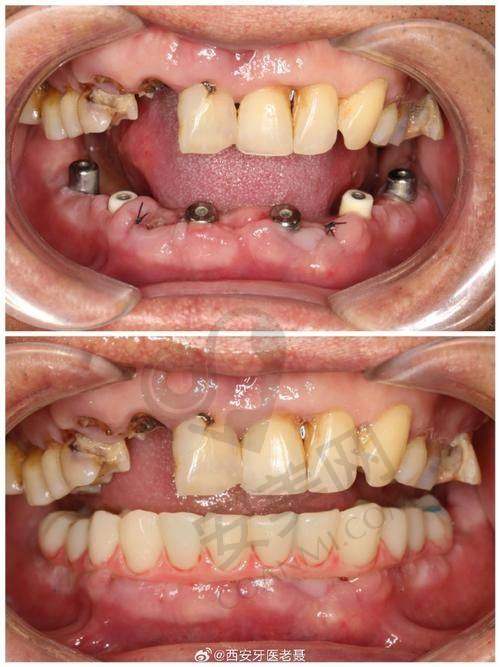

终于到了种植牙手术的那天,我心里还是有点紧张的。医生给我打了局部麻醉,在麻醉生效后才开始手术。整个手术过程中,我并没有感觉到明显的疼痛,只是能感觉到医生在操作。医生的技术非常娴熟,动作特别轻柔,每一个步骤都特别精细。手术持续了大概一个多小时,结束后,医生详细地跟我交代了术后的注意事项,比如要注意口腔卫生、避免吃辛辣刺激的食物等。术后,麻醉药效过了之后,确实有一些轻微的疼痛和肿胀,但都在可以忍受的范围内。医生给我开了一些消炎药和止痛药,按照医嘱服用后,疼痛和肿胀特别快就缓解了。

宿州康桥口腔医院的种植牙技术有特别多特色之处。首先,他们采用的是精良的种植系统,这些种植体的材质非常好,生物相容性高,能够与牙槽骨更好地结合,提高种植牙的成功几率。其次,医院拥有专精的医生团队,他们都有丰富的临床经验,能够根据患者的具体情况制定更适合的种植方案。而且,医院还引进了精良的数字化种植技术,通过计算机模拟种植过程,能够更精细地确定种植体的位置和角度,减少手术创伤,缩短手术时间。另外,医院的服务也非常贴心,从术前的询问、检查,到术中的治疗,再到术后的回访和维护,都有专人跟进,让患者感受到全方面的关怀。

在术后的修复期间,我严格按照医生的嘱咐进行护理。每天早晚认真刷牙,使用漱口水保持口腔清洁。饮食方面,我也特别注意,尽量吃一些软烂、易消化的食物。大概过了几个月,种植体与牙槽骨已经完全结合,医生为我安装了牙冠。戴上牙冠后,我感觉就像自己原来的牙齿一样,非常自然,而且咀嚼功能也修复得良好。现在,我可以像以前一样正常吃东西了,再也不用担心牙齿缺失的问题了。